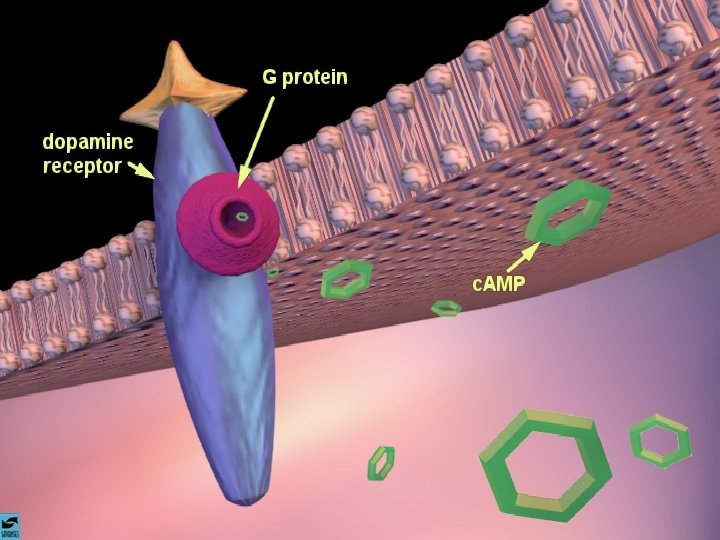

ANFETAMINAS E COCAÍNA EFEITOS CEREBRAIS: ATIVA OS SISTEMAS DOPAMINÉRGOS MESOLÍMBICOS E MESOCORTICAIS, INIBINDO A RECAPTAÇÃO DE DOPAMINA NOS TERMINAIS SINÁPTICOS E PROMOVENDO SUA LIBERAÇÃO NAS SINAPSES.